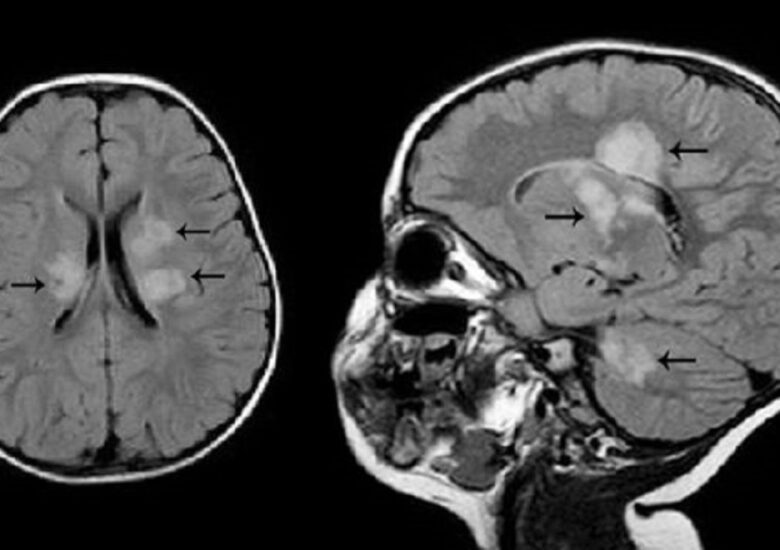

Este scleroza multiplă ereditară? Alți factori, în afară de ADN-ul tău, sunt în joc

Scleroza multiplă (SM) nu este o boală direct moștenită. Acest lucru implică faptul că SM nu se transmite definitiv de-a lungul generațiilor unei familii (de exemplu, nu veți dezvolta automat